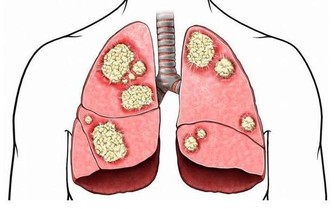

實際上,目前我們已經發現了數百種癌症,每個都具有獨特的分子特徵和可變的臨床表達。比如,在神經腫瘤學中,已經確定了至少120種腦和脊髓癌亞型。對於這種多樣化的敵人,我們的診斷和治療方法必須擴大,也必然很難。

4. 擁有“癌症基因”意味著你注定要患癌症

即使你的直系親屬中有人患過癌症,即使你身上已經出現基因突變,也不是無法避開癌症的。我們的新陳代謝和細胞中有許多錯綜複雜的途徑,其中一些途徑可以打開基因,有些可以將它們關閉。這是一個叫做“表觀遺傳學”的領域,環境和外部影響可以改變基因表達。於是,這使得患者有能力做一些事情,比如吃健康的飲食和鍛煉,這可能會影響最終結果。